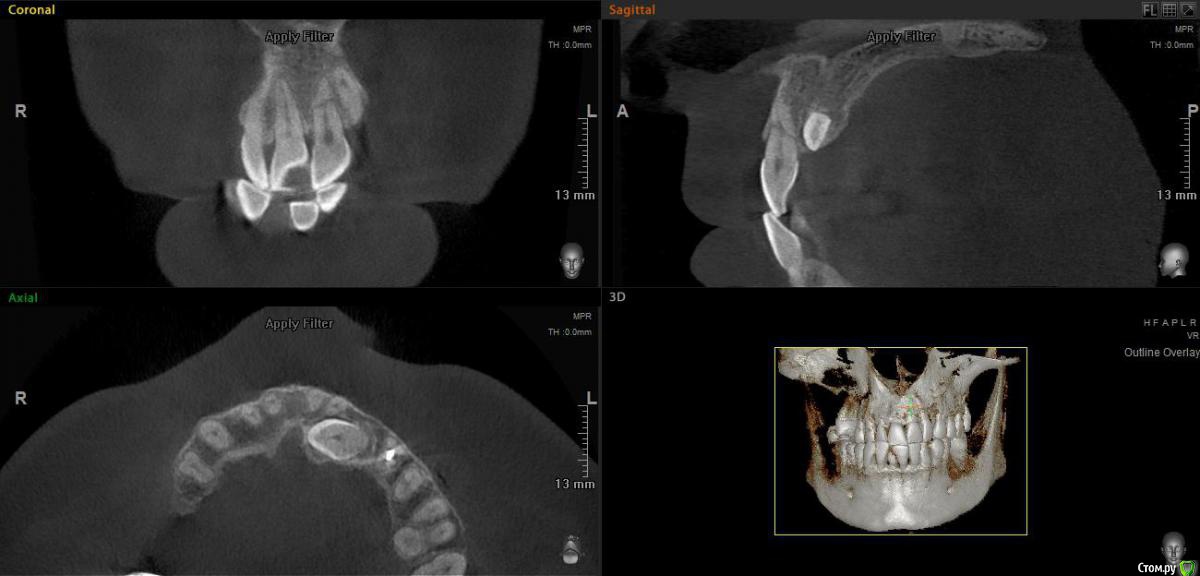

elen_only Опубликовано 10 февраля, 2020 Поделиться Опубликовано 10 февраля, 2020 (изменено) Доброго дня всем,коллеги! Всех с прошедшим днем стоматолога! Ситуация такая:направил ко мне ортодонт на резекцию верхушки корня молодого мужчину. В анамнезе травма передних зубов,лет 10 назад. Год назад поставили брекет-систему. Иногда жалуется на небольшую болезненность при накусывании. Зуб подвижен,в цвете не изменён. Прикрепляю снимки,разница между первым и вторым-год. Доктор не заметила перелом корня зуба 21 и поставила брекеты. Удалить зуб и вкрутить сразу имплантат (как хотелось бы) не получится,у пациента ретинированный клык,который будут пытаться вытянуть. В связи с этим вопрос: как сохранить этот зуб,хотя бы до момента ,когда вытянут клык? Думала запломбировать верхнюю часть и удалить верхушку,но в общем-то за год никаких периапикальных изменений не появилось,кроме резорбции отломков,может и не трогать ее. Как правильнее поступить?1.запломбировать верхнюю часть,не трогать верхушку2. Запломбировать верхнюю часть и удалить верхушку3. Вообще не трогать зуб,сколько постоит.И если пломбировать,то чем? И как мыть эту часть гипохлоритом,чтобы не вышел куда не надо? Изменено 10 февраля, 2020 пользователем elen_only Ссылка на комментарий

elen_only Опубликовано 10 февраля, 2020 Автор Поделиться Опубликовано 10 февраля, 2020 Коронковый фрагмент витальный?На холод реагирует,в цвете не изменен. ЭОД,увы,нет возможности проверить.между снимками год разницы,периапикальных изменений не появилось Ссылка на комментарий